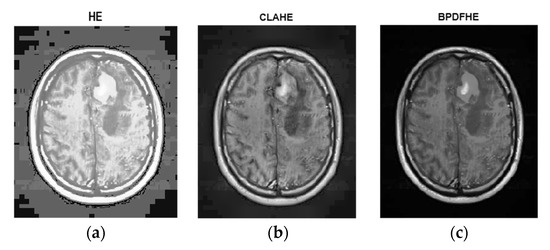

The following figures are the enhanced images with their corresponding histograms (HE, CLAHE, and BPDFHE) for the original images.

Figure 4a is the original. Figure 4b is its histogram representation. Figure 5a–c represents the same image enhanced via different preprocessing methods, i.e., HE, CLAHE, and BPDFHE, and Figure 6a–c is their respective histograms.

Figure 5.

Preprocessed with (a) HE, (b) CLAHE, and (c) BPDFHE.

Figure 7a is the original image. Figure 7b is its histogram representation. Figure 8a–c represents the same image enhanced via different preprocessing methods, i.e., HE, CLAHE, BPDFHE, and Figure 9a–c is their respective histograms.

Figure 8.